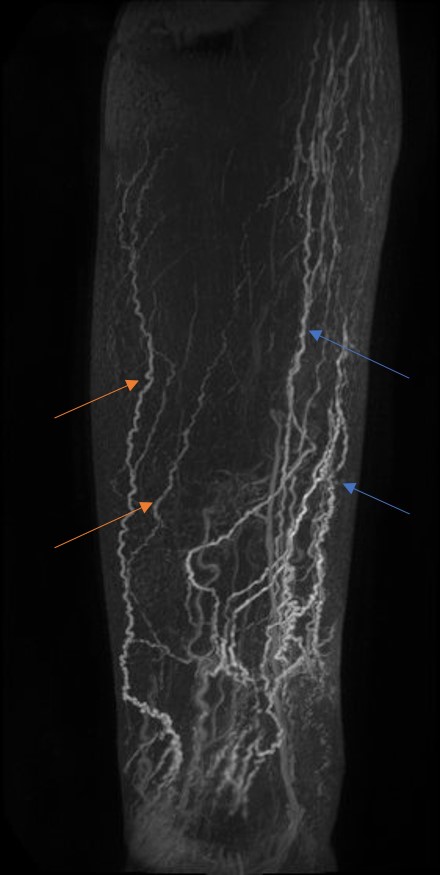

Figure 2 Lower limb coronal maximum intensity projections of the right leg of a lymphoedema patient with a FOXC2 genotype demonstrating multiple medial (blue arrows) and lateral drainage routes (orange arrows).

Figure 3 Subtracted sagittal (A) and unsubtracted transverse DCE-MRL (B) maximum intensity projections of the right leg of a lymphoedema distichiasis patient demonstrating posterior lymphatic contrast drainage (blue arrows) and the extravasation of contrast agent from larger collecting vessels back to the dermal capillaries (orange arrows), also known as dermal rerouting. This dermal rerouting can be seen with improved spatial resolution in the Indocyanine Green Lymphogram image (mid-tibia) of the same limb (C), but obscures larger lymphatic vessels lying behind this region.